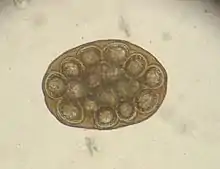

Dipylidium caninum egg packet